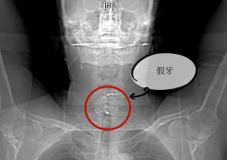

65岁的王叔叔吃饭时不慎误吞整排带铁钩假牙,咽喉痛,进食困难,就诊当地医院,用胃镜、食道镜等多次尝试后无法取出,马上转诊至我院。经过喉镜、颈部CT等相关检查,发现异物为钩状体积大假牙,横跨喉咽及食道,钩体已深入食道造成损伤,局部组织水肿明显,异物若未及时取出将出现呼吸梗阻,合并感染将出现脓肿可能,生命危在旦夕。

术中看到异物为大体积钩状,爪钩像八爪鱼一样横跨喉咽部及食道入口,钩体已致食道穿孔,在耳鼻咽喉科杨心青主任医师、陈勇主任医师、王晓燕副主任医师、许玲玲医师及麻醉科丘春华副主任医师的配合下,通过直达喉镜、弧形喉镜、扩展喉镜联合食道镜多次更换配合“接力”,成功取出异物,避免了颈外入路取异物的创伤。术后王叔叔因喉部水肿送入重症医学科进一步治疗,3天后顺利出院。

卡在王叔叔咽喉中的假牙终于被取出